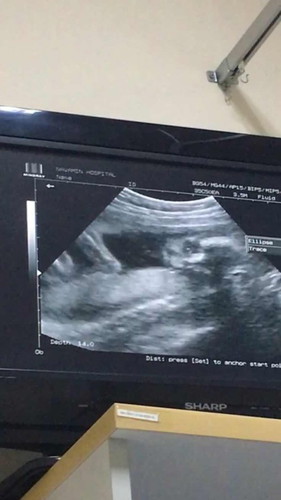

หมอเเจ้งว่าน้องกลับหัวเเล้ว ตอนนี้24วีค#ท้องแรก กลับหัวไวไปไหมคะ เสี่ยงอะไรไหม

การที่น้องกลับหัวเร็วไม่มีความเสี่ยงค่ะแม่ ไม่ต้องกังวลนะคะ